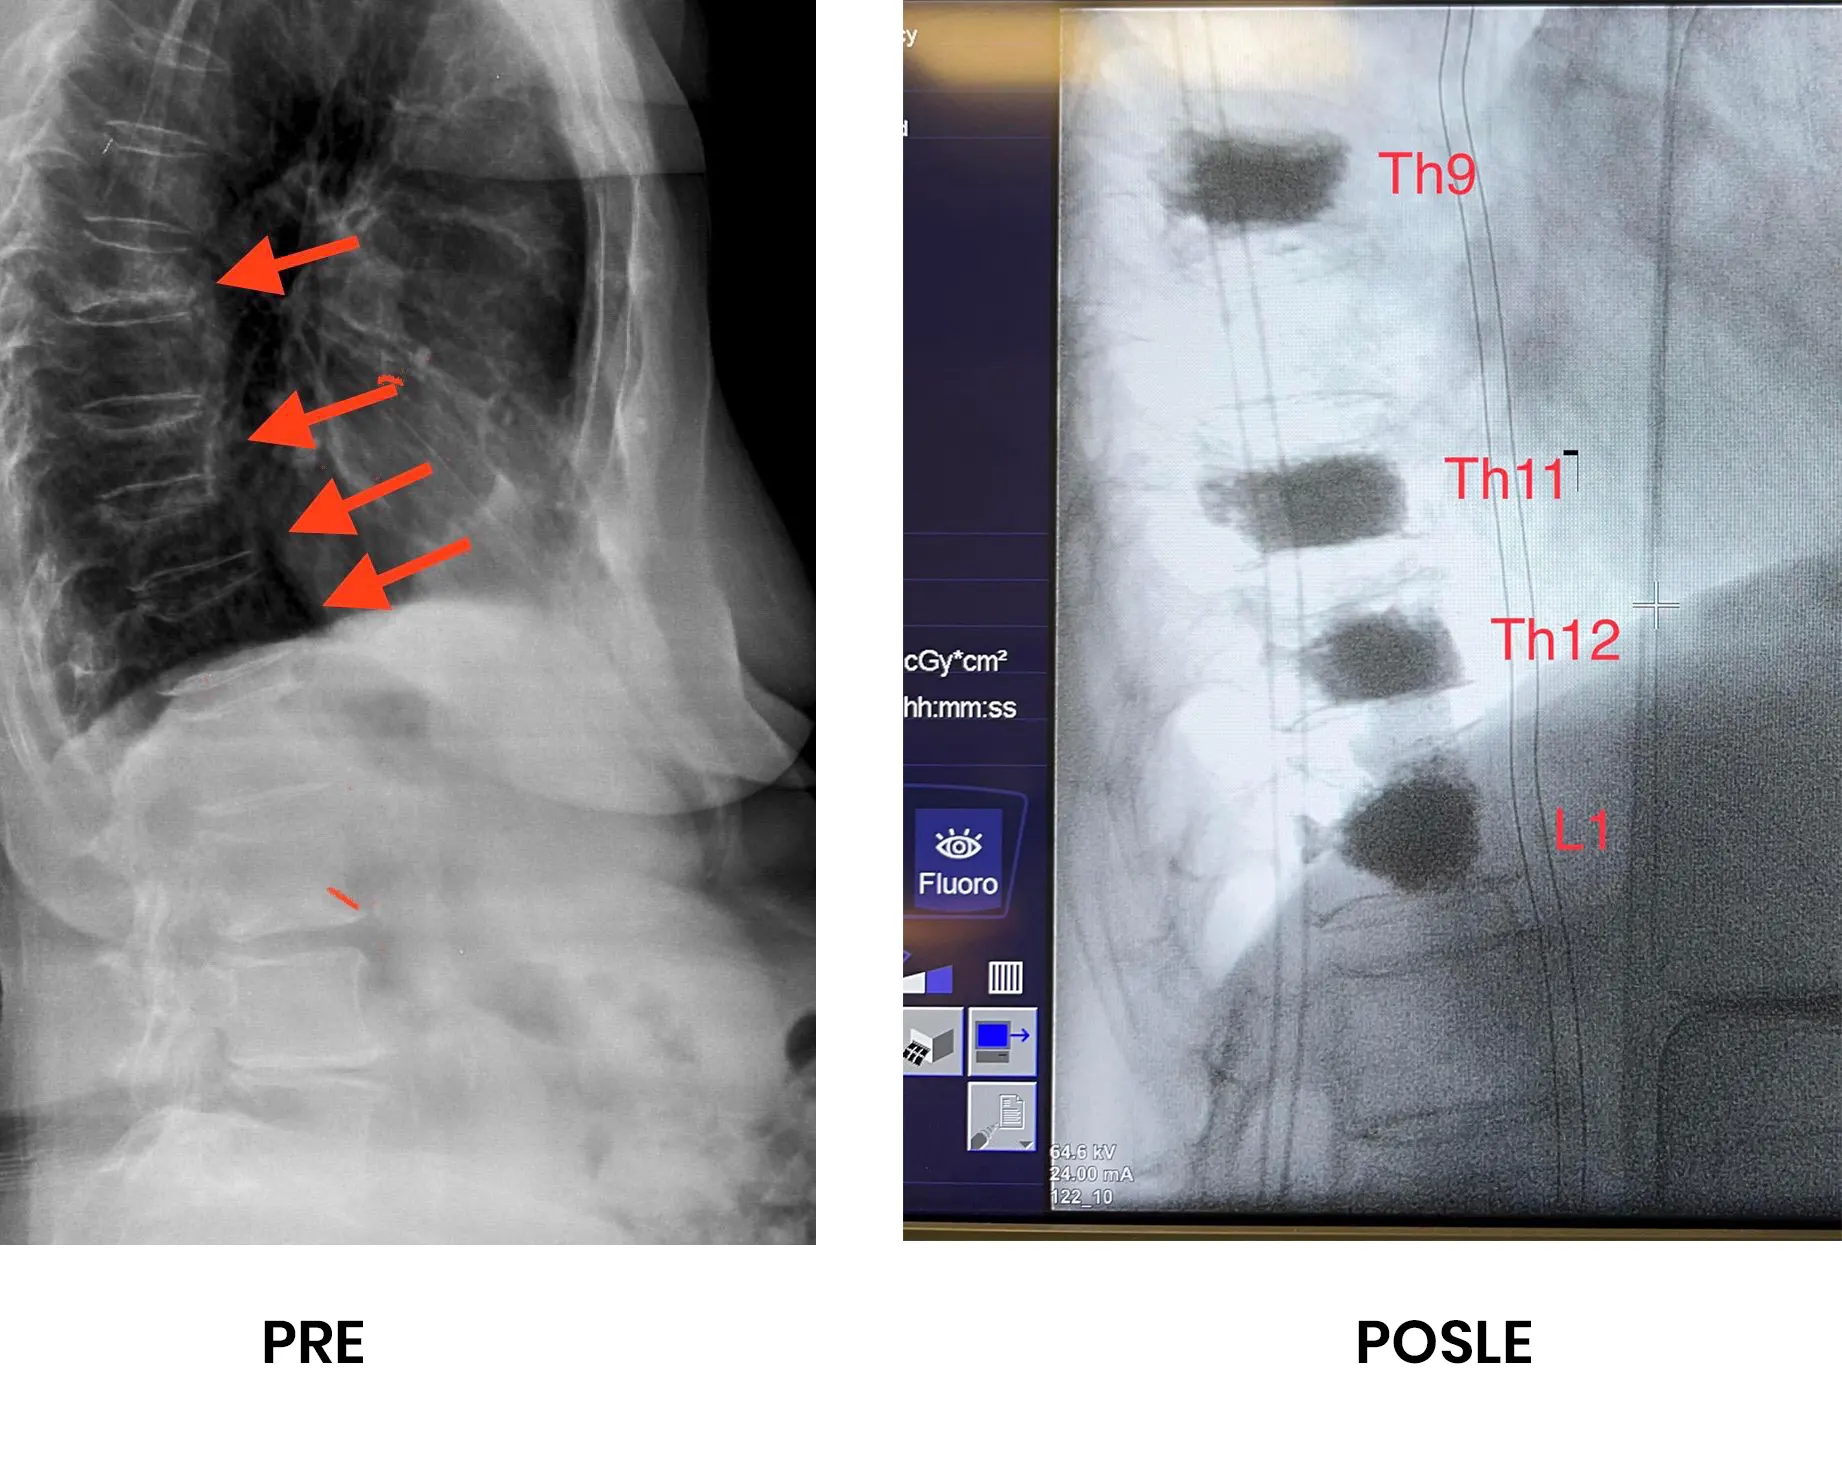

Pacijentkinja od 83 godine, sa naglo nastalim nepodnošljivim bolom u leđima. Ima dokazanu osteoporozu. MR i RTG kičme pokazao je postojanje kompresivnih preloma četiri pršljena, zbog generalizovanja osteoporoze.

Perkutana vertebroplastika kod preloma kičme zbog osteoporoze.